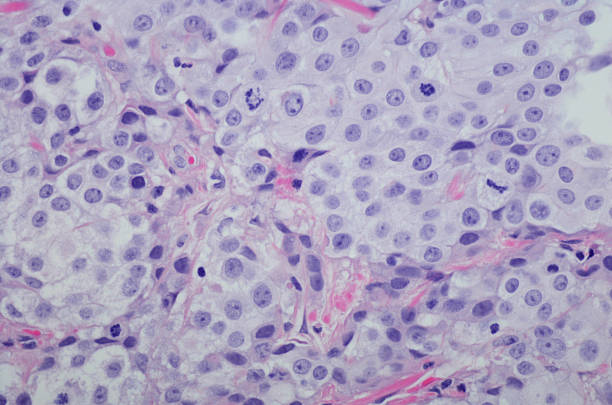

방광암은 방광 내부에 악성 종양이 생긴 것을 말합니다. 이 종양은 방광 벽에서 시작하여 방광 내부로 침입할 수 있으며, 심각한 경우 다른 조직이나 기관에도 전이될 수 있습니다.